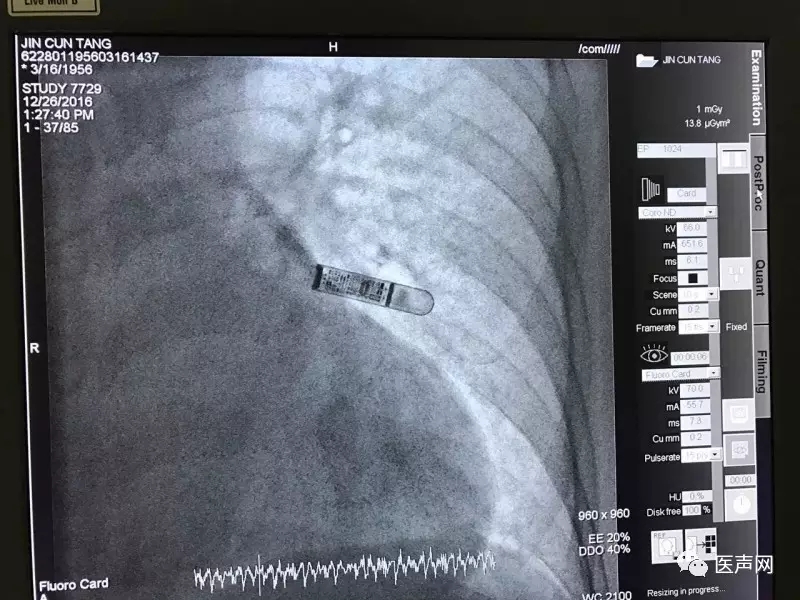

手术时间:2016.12.26

选取位置:胸骨左缘2cm,与胸骨成45度

植入经过:消毒铺巾后,在植入位置以特制手术刀切开皮肤,使用分离工具两次分离皮下组织形成植入通路,最后以注射工具注入Reveal LINQ。手术过程顺利,持续5分钟,切口细微。

术中程控:术中程控R波振幅: 0.94mv,位置良好。

手术影像 :